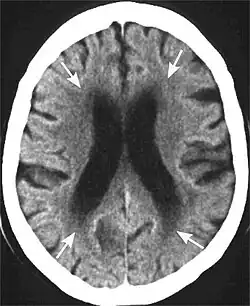

Head CT showing periventricular white matter lesions.

Leukoaraiosis is a particular abnormal change in appearance of white matter near the lateral ventricles. It is often seen in aged individuals, but sometimes in young adults.[1][2] On MRI, leukoaraiosis changes appear as white matter hyperintensities (WMHs) in T2 FLAIR images.[3][4] On CT scans, leukoaraiosis appears as hypodense periventricular white-matter lesions.[5]